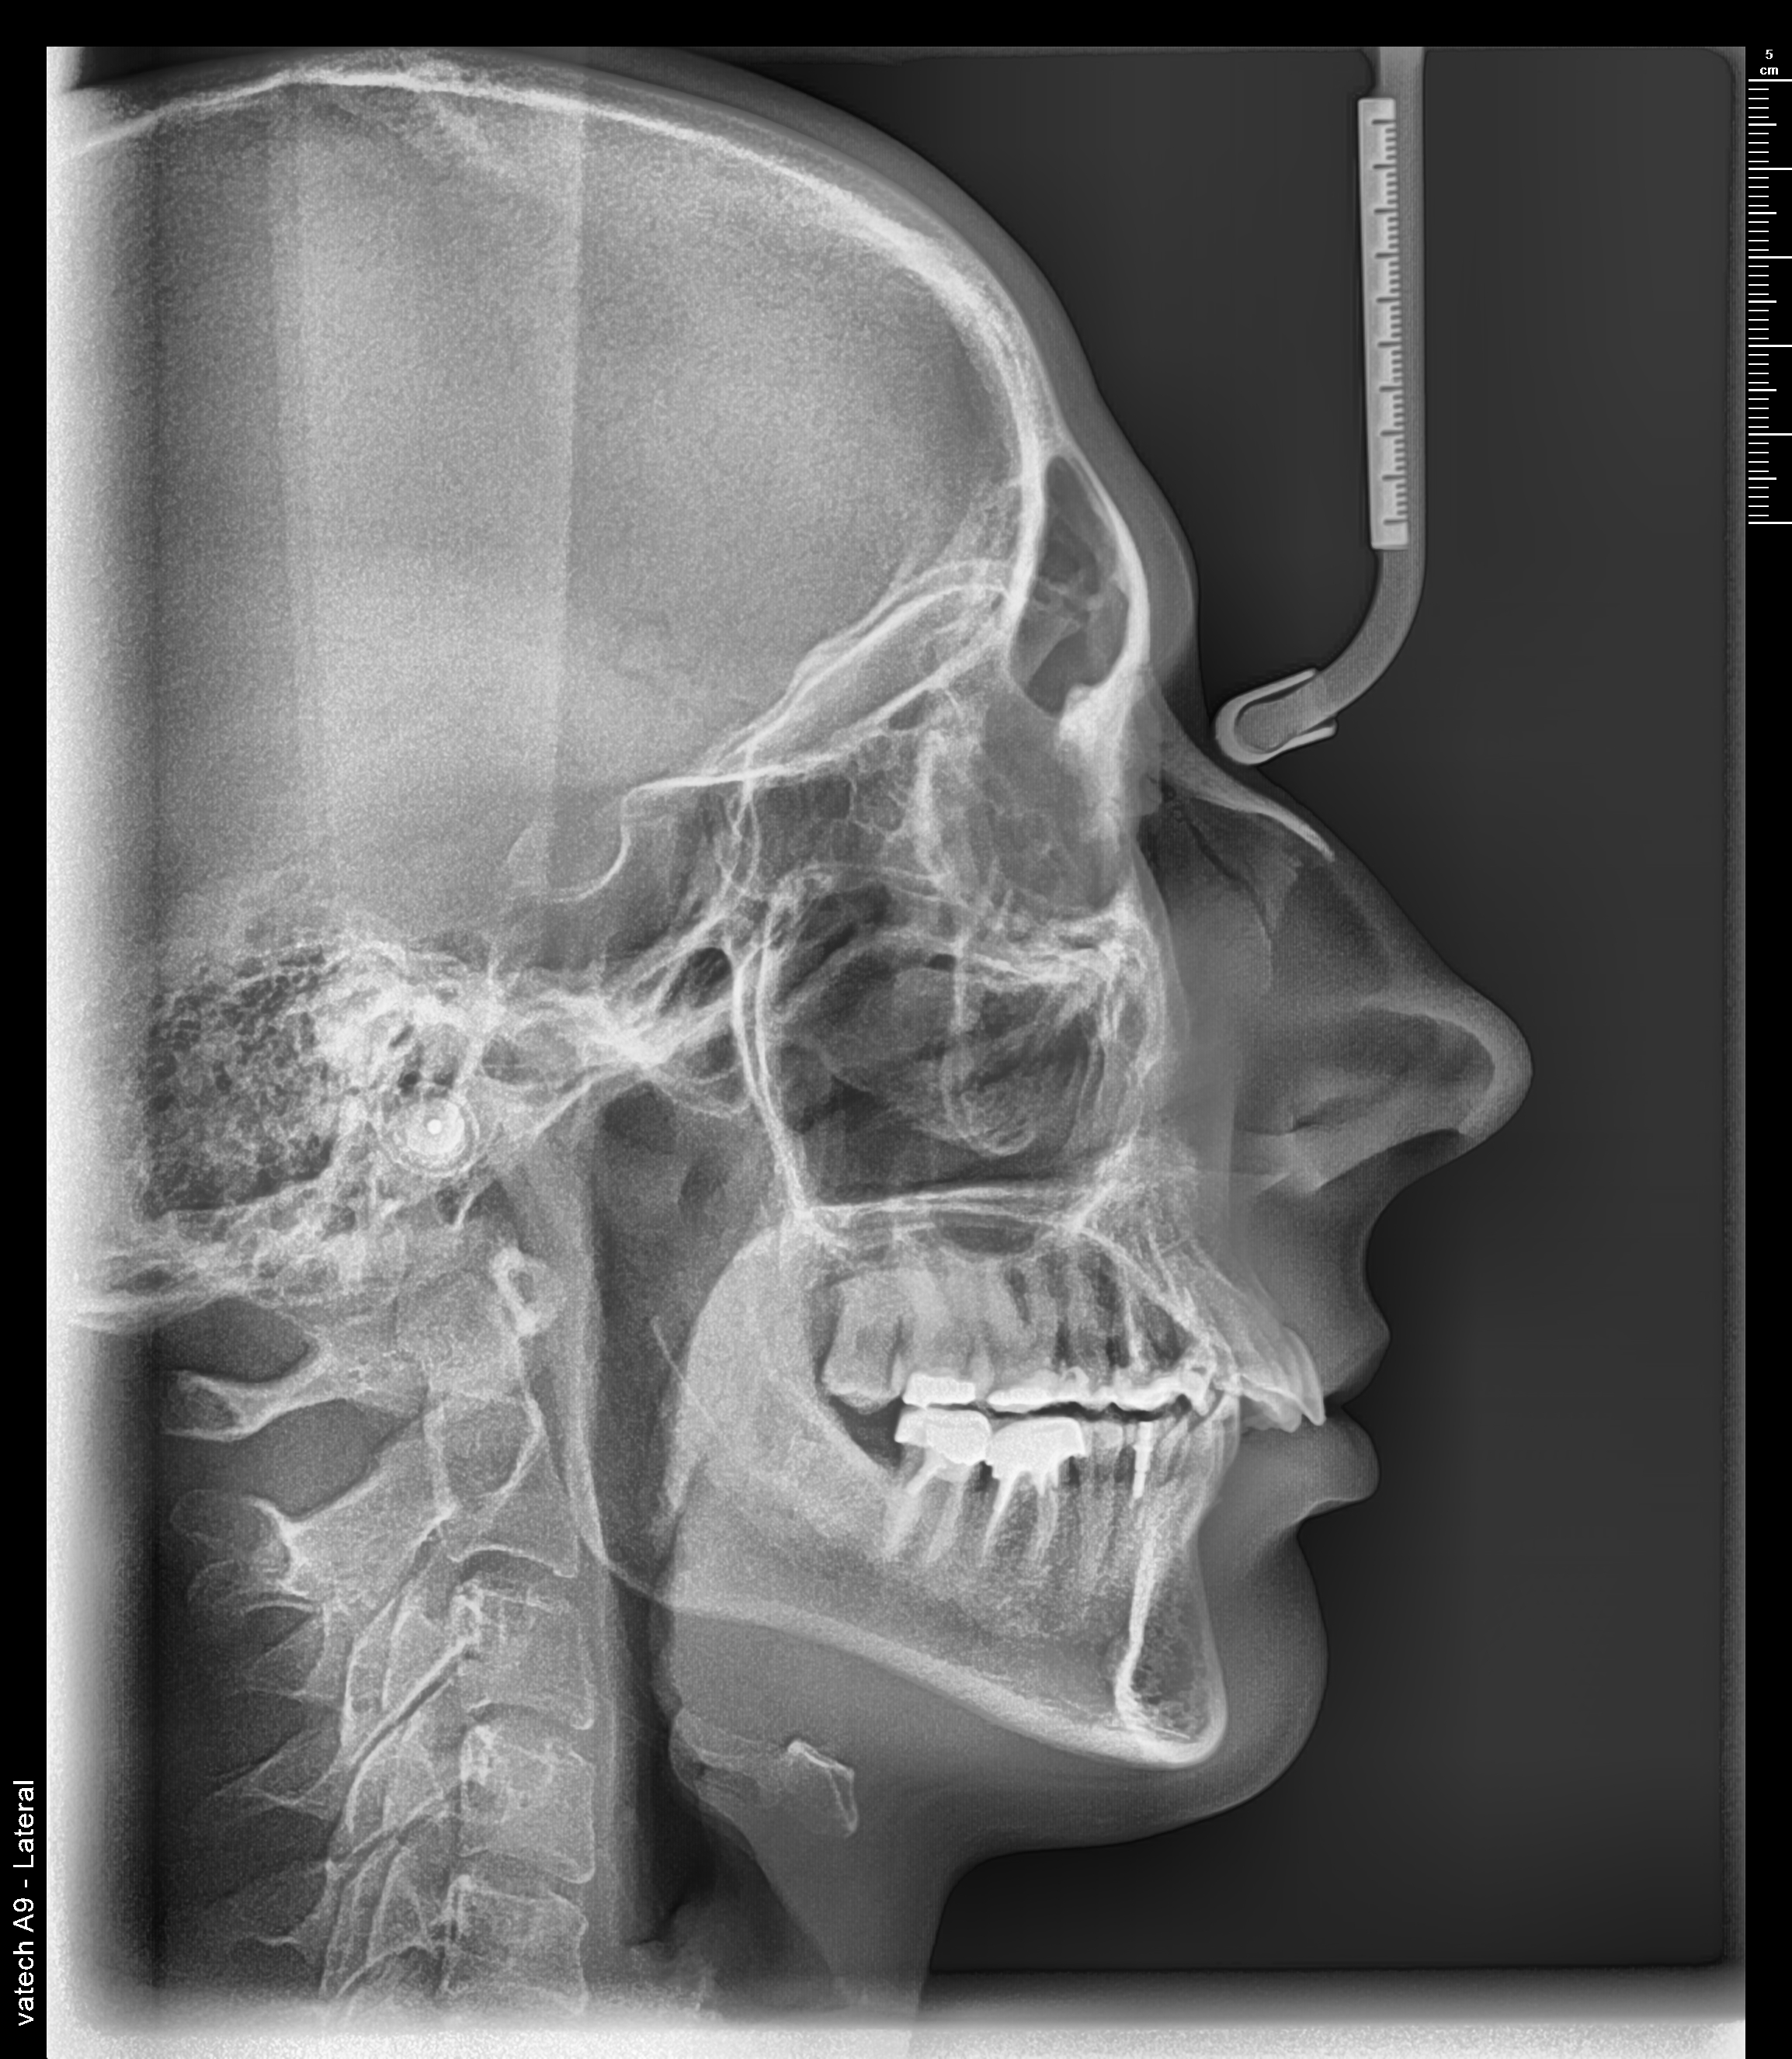

Телеренгтгенография

точна диагностика за ортодонтски и лицево-челюстни нужди.